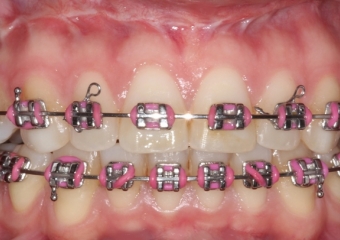

Mordida após a cirurgia